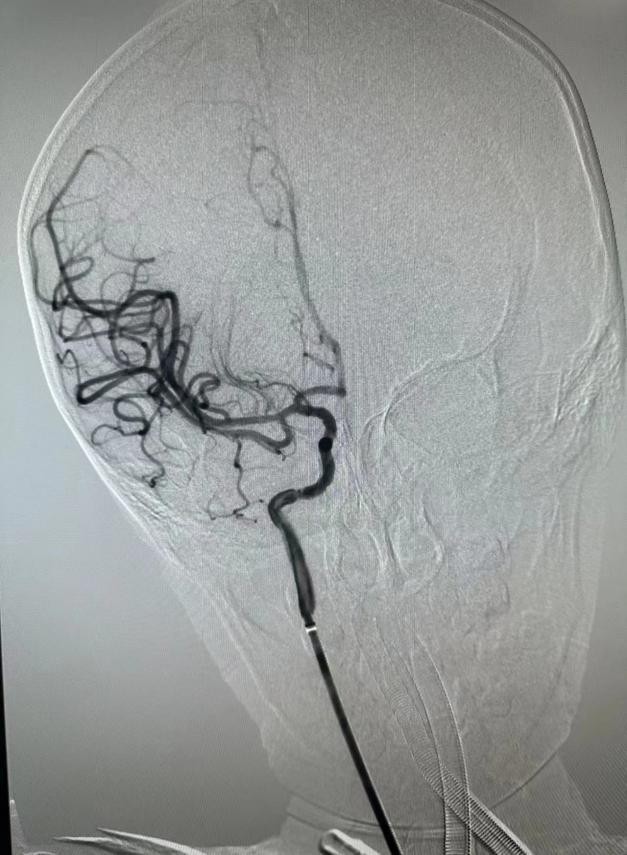

在麻醉科、小儿重症医学科等专业人员床旁监护下,介入团队成功在患儿脑组织窗内进行介入手术,在右股动脉取0.27cm的微小通路,同时置入100cm的导管进行脑血管造影后,明确右侧大脑中动脉起始段闭塞,随后使用专用的脑血栓抽吸装置缓慢抽吸血栓,在经历了90分钟的手术后,成功取出患儿“肇事血栓”,右侧大脑中动脉前向血流恢复,为患儿疏通了“生命河流”。

取栓成功后